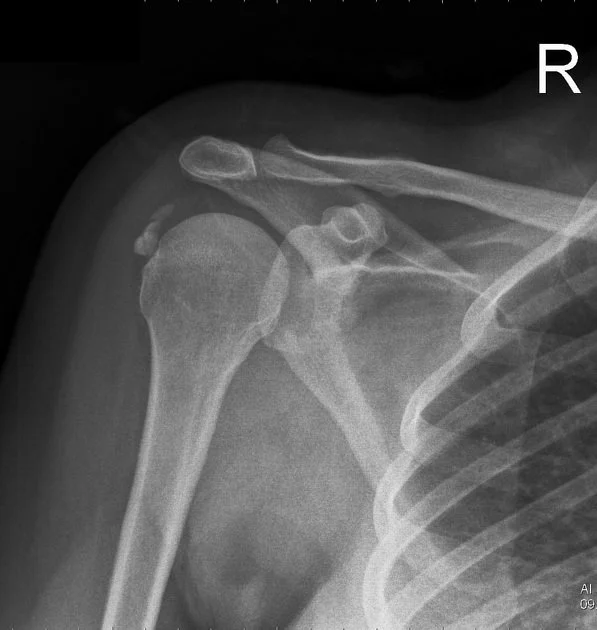

X-ray image of a right shoulder showing a fractured clavicle and dislocated humeral head.